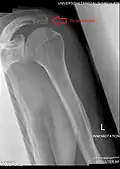

Os acromiale

The acromion has four ossification centers called (from tip to base) pre-acromion, meso-acromion, meta-acromion, and basi-acromion. In most cases, the first three fuse at 15–18 years, whereas the base part fuses to the scapular spine at 12 years. However, in between 1% and 15% of cases, this osseous union fails and the acromion remains separate as an accessory bone. This condition is referred to as os acromiale, but rarely causes pain. Earlier estimates of its prevalence were as low as 1.4%, and this higher estimate was made by Sammarco in the year 2000, based on radiographic and anatomical studies.[6][7]

Although historically regarded as an incidental finding, the os acromiale may occasionally produce symptoms from subacromial impingement or instability at the site of non-union.[9] In people with symptoms of os acromiale, dynamic ultrasound sometimes shows hypermobility in the area during shoulder movement, or graded compression with the probe.[10]

Radiograph of the shoulder showing an os acromiale